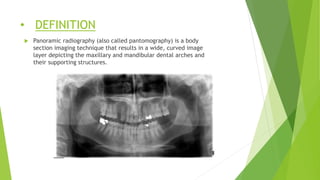

• DEFINITION

 Panoramic radiography (also called pantomography) is a body

section imaging technique that results in a wide, curved image

layer depicting the maxillary and mandibular dental arches and

their supporting structures.